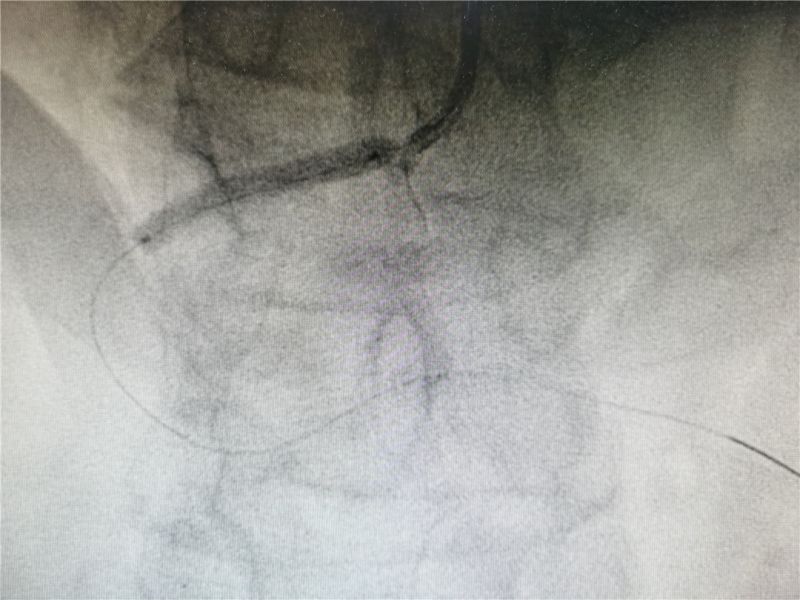

术中